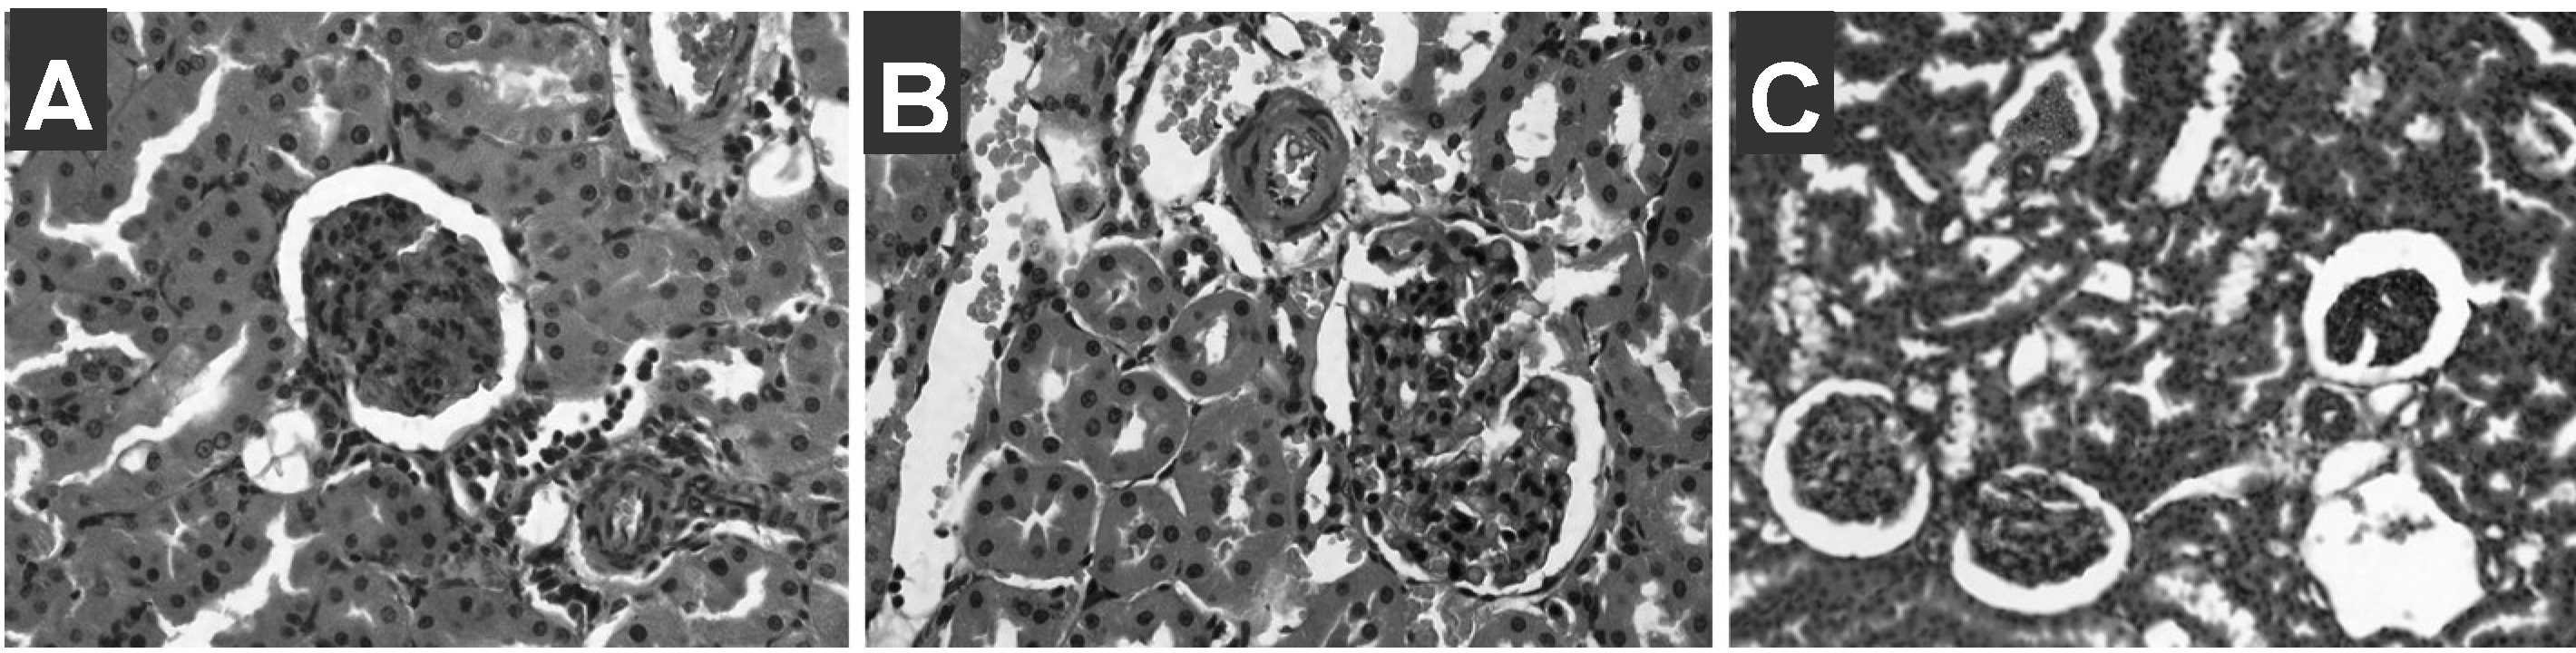

3.3 Tissue staining